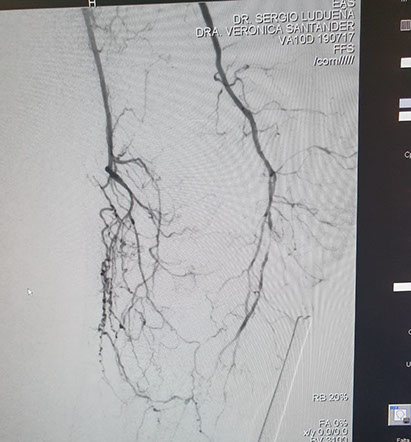

Las imágenes siguientes son previas al procedimiento y posterior se ve ambas arterias tíbiales permeables, y circulación en el pie

El procedimiento lo realizo el equipo de Hemodinamia de INCOR dirigido por el Dr. Ludueña junto con la intervención del Dr. Alejandro Flores (Flébologo y cirujano vascular)